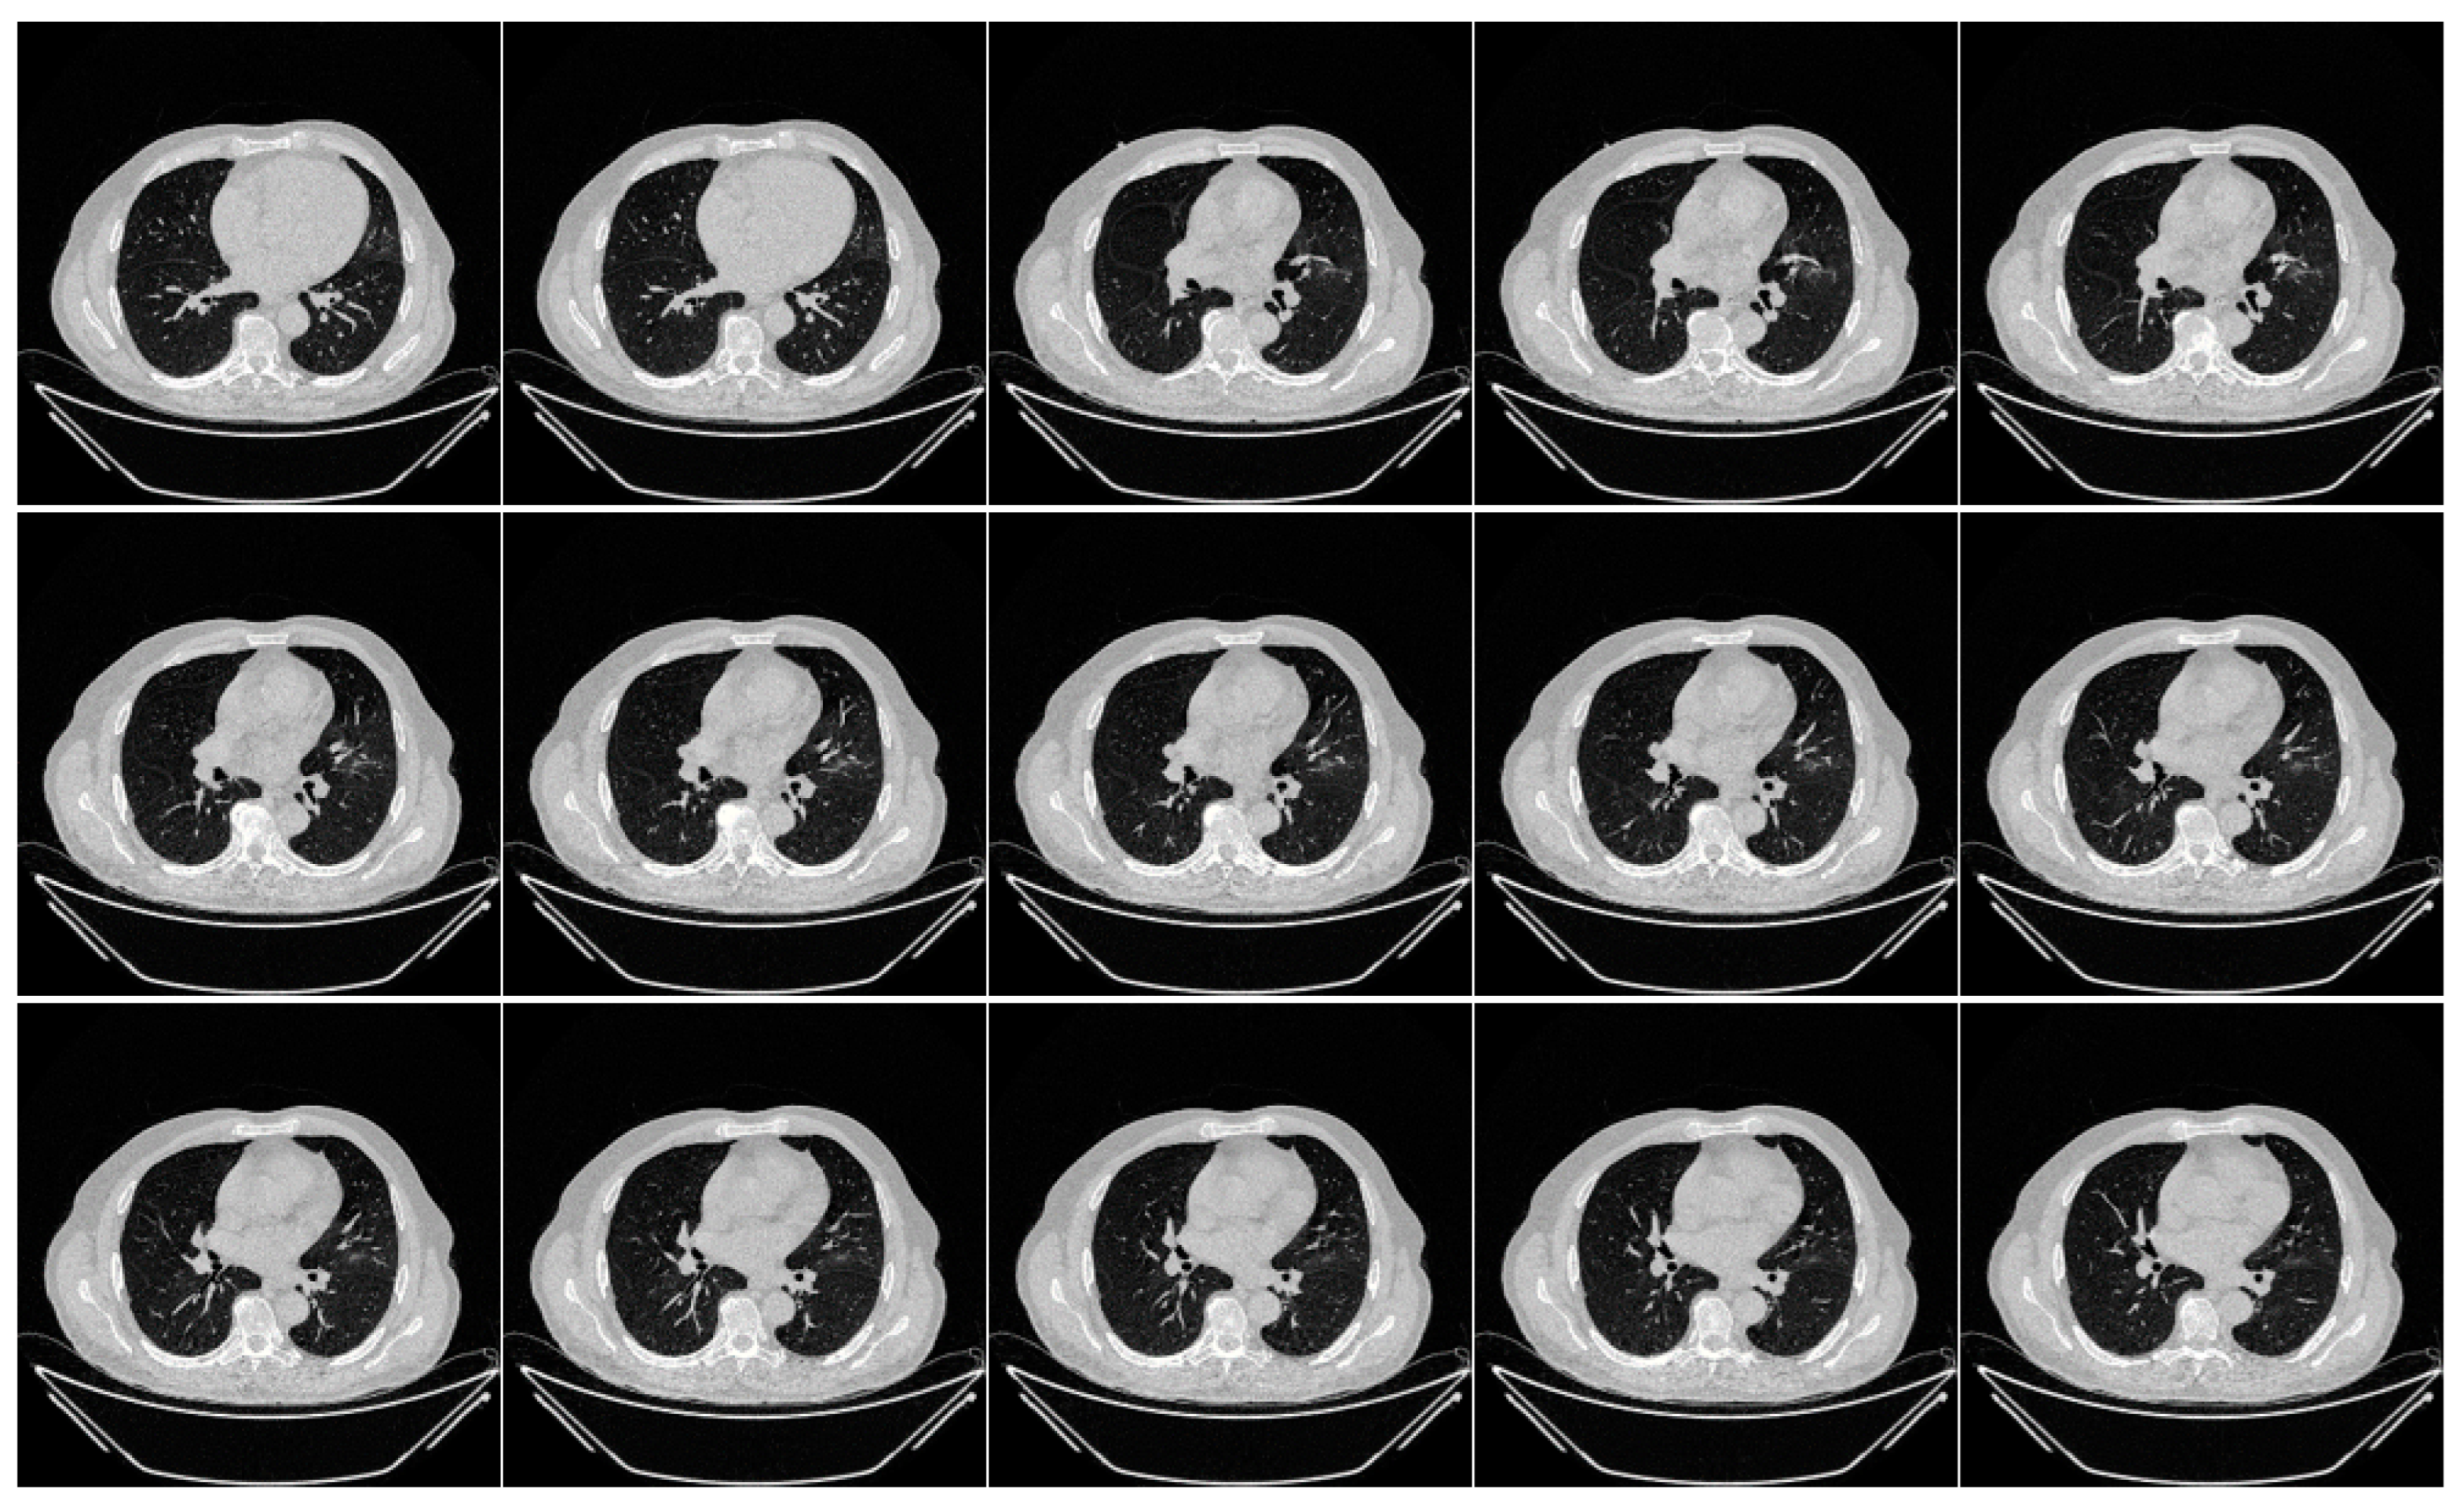

The second data set included 72 NovMED COVID-19-positive individuals. Figure 2 included 47 males, and the remainder were female. An RT-PCR test was conducted to confirm the presence of COVID-19 in the selected cohort, with an average value of approximately 2.4 GGO, consolidation, and other opacities. Of the 72 NovMED patients, 61% had a cough, 9% had a sore throat, 54% had dyspnea, 42% had hypertension, 12% were diabetic, 11% had COPD, and 11% were smokers. In total, 10 patients died due to COVID-19 infection in this cohort. Figure 3 shows NovMED(control) datasets from Italy. The COVID (Croatia) dataset had dimensions of 512 × 512 and 5396 raw images, COVID (ITA) had dimensions of 768 × 768 and 5797 raw images, and control (Italy) had dimensions of 768 × 768 and 1855 raw images.

Figure 2.

Raw “COVID-19 CT slices” images taken from NovMED dataset.

Figure A2.

Raw “Control CT slices” taken from NovMED Dataset.